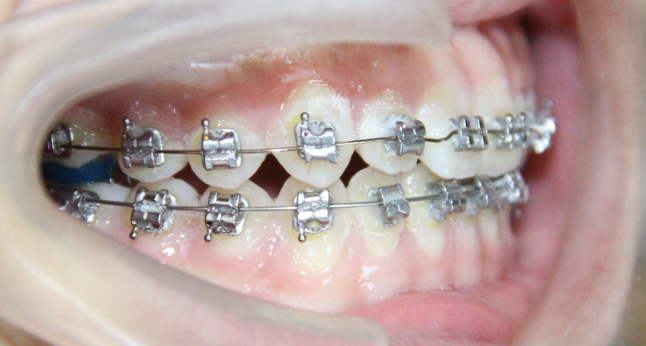

病例2

治疗前

治疗后